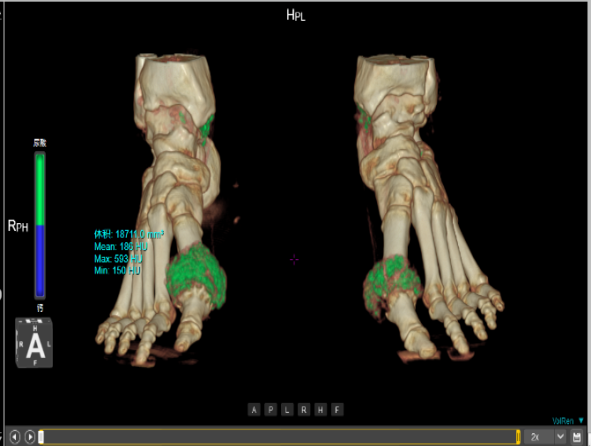

功能成像方案

能谱成像技术:分析人体病灶的组织成分、组织特性,为影像诊断提供常规CT无法提供的重要信息,如进行痛风石检测、泌尿系结石成分分析、碘与钙质区分、肿瘤同源性鉴别等。

痛风石检测

联影ct怎么样【小南快讯】辐射低、成像快、更精确!CT届的“天花板”——320排640层超高端CT落户奉中心!_https://www.jmylbn.com_新闻资讯_第18张

泌尿系结石成分分析

联影ct怎么样【小南快讯】辐射低、成像快、更精确!CT届的“天花板”——320排640层超高端CT落户奉中心!_https://www.jmylbn.com_新闻资讯_第19张

肿瘤同源性鉴别

联影ct怎么样【小南快讯】辐射低、成像快、更精确!CT届的“天花板”——320排640层超高端CT落户奉中心!_https://www.jmylbn.com_新闻资讯_第20张